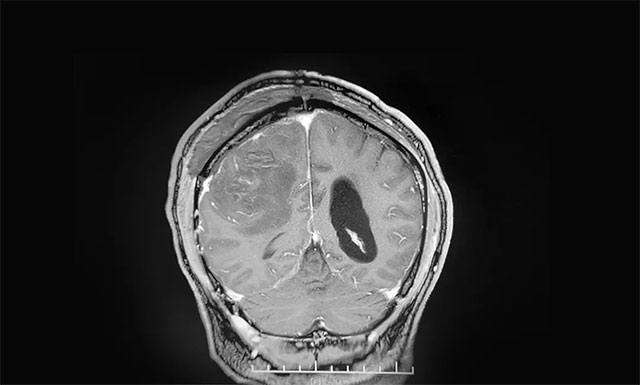

▲ 术后影像显示肿瘤被切除

术后,患者手术恢复良好,未出现偏瘫、失语等,左侧肢体麻木消失,肢体活动较之前明显改善,说话较之前流利许多。目前患者还在康复中,再过一段时间即可出院。